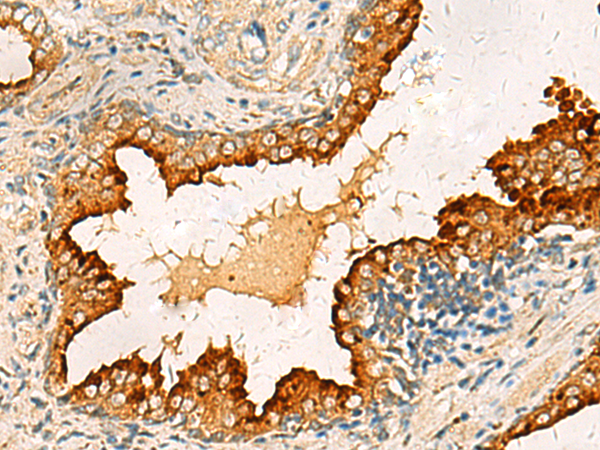

分类: 科研抗体货号: P03373别名: FBS; DC10; FBX8应用: IHC反应种属: Human, Mouse